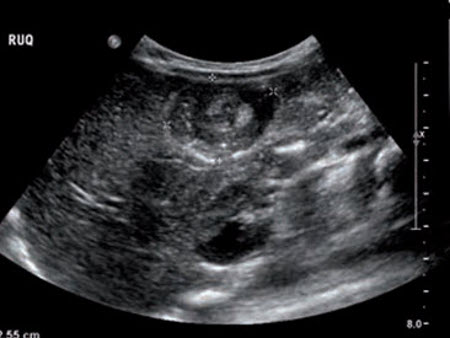

Colecistite: ultrassonografia de colecistite aguda e presença de cálculos biliares

Do acervo de Dr. Charles Bellows

Ultrassonografia de colecistite aguda e presença de cálculos biliares: a seta aponta para um cálculo no fundo da vesícula biliar, com sua sombra ecogênica abaixo

Cortesia de Charles Bellows e W. Scott Helton; usado com permissão